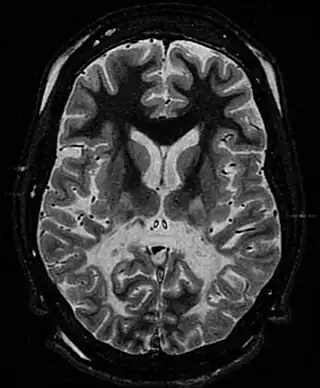

![]() Sustancia blanca, con volumen reducido y aumento de la intensidad de la señal. La sustancia blanca anterior está respetada. Las características son compatibles con la adrenoleucodistrofia ligada al cromosoma X. | ||